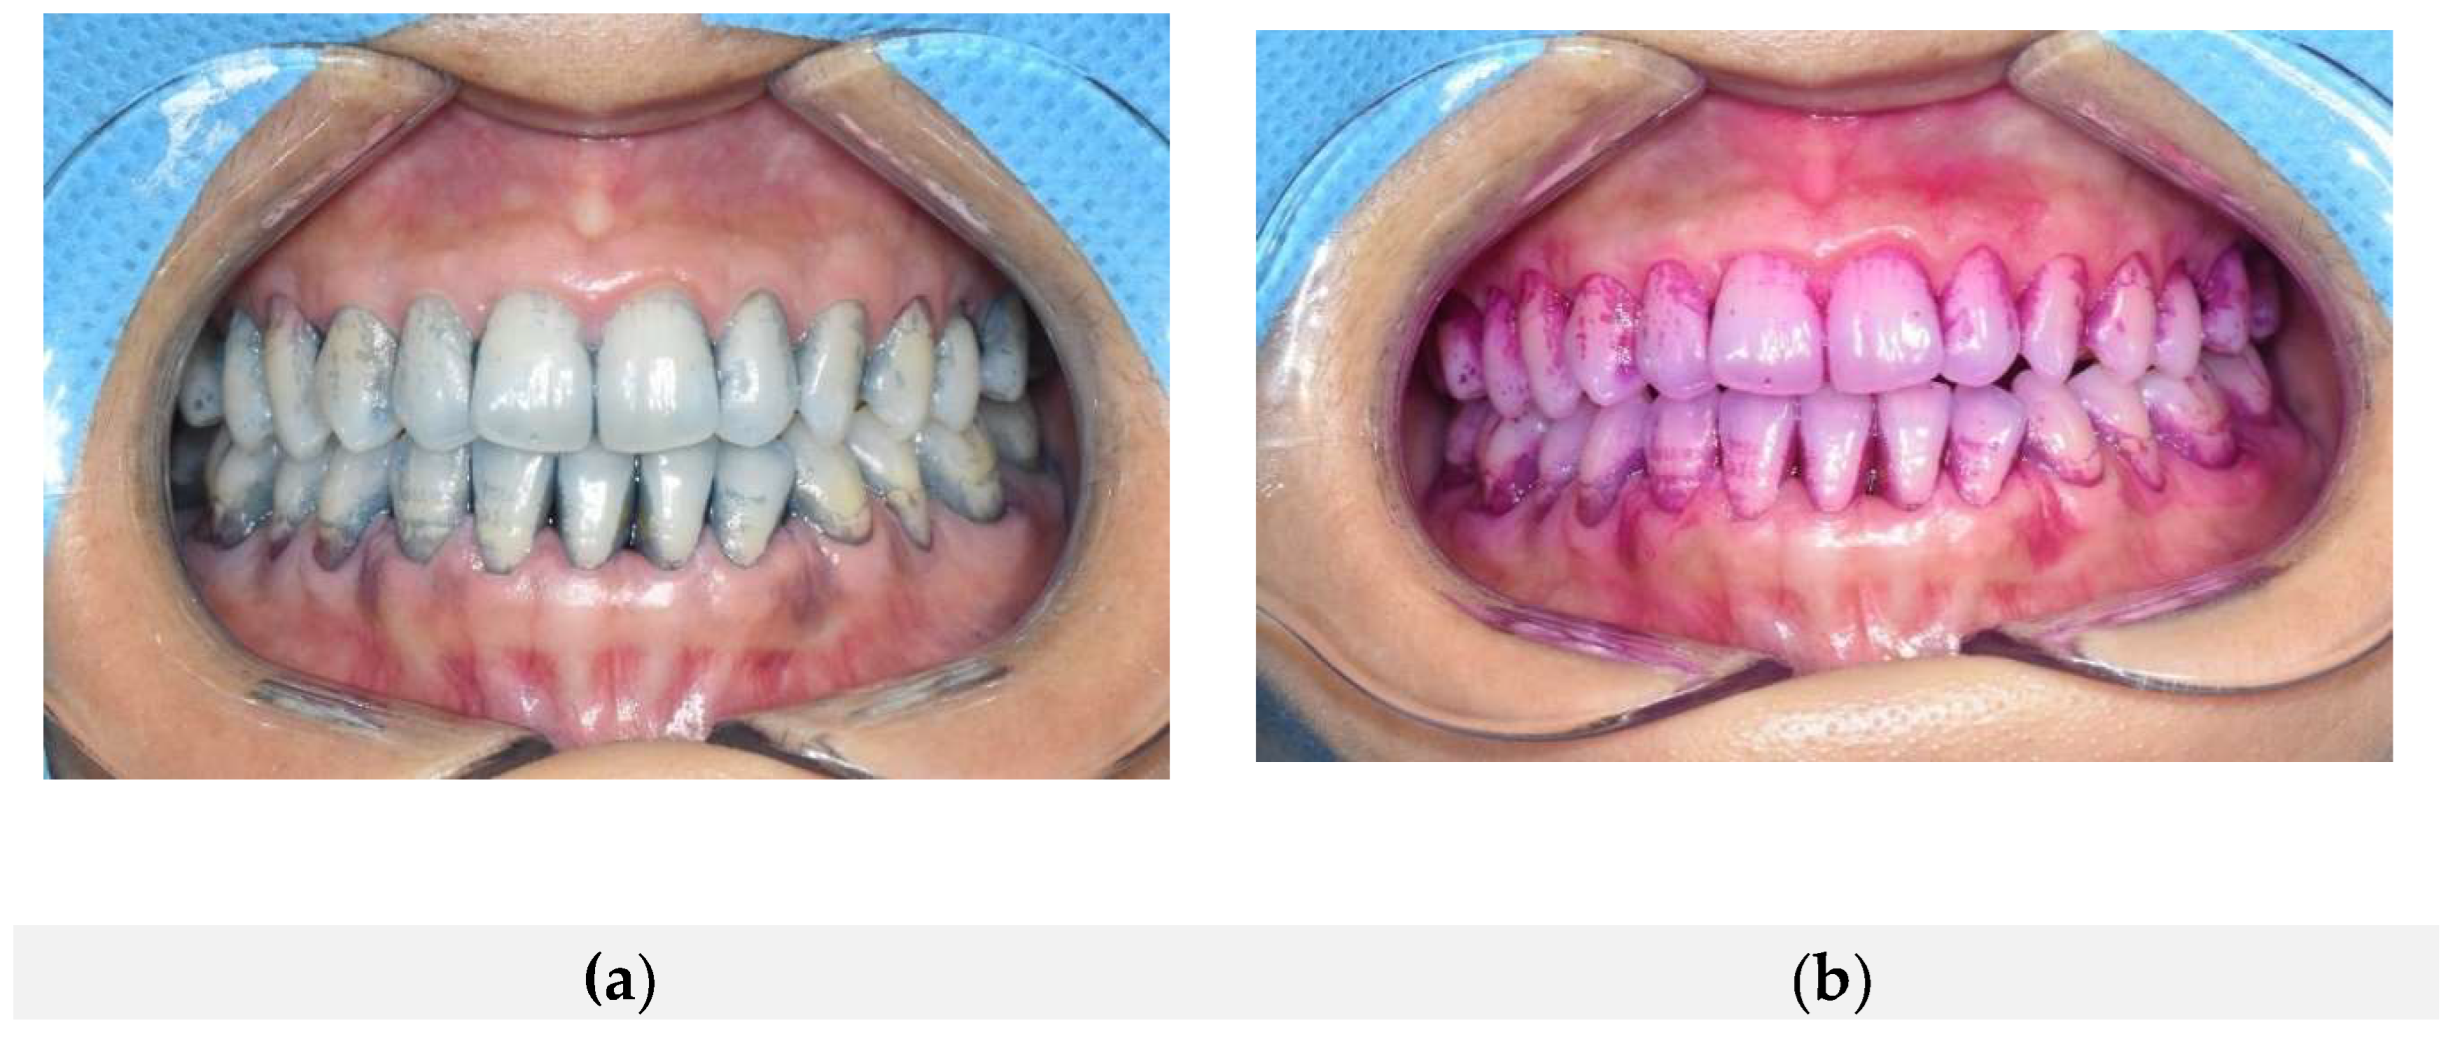

Figure 3 shows intraoral comparative photographs of the same participant, first after applying the conventional plaque-disclosing agent, followed by the natural dye-based plaque-disclosing agent. Panel (a) illustrates the staining pattern after the conventional disclosing agent application, and panel (b) shows the result following subsequent application of the natural dye-based agent. Both agents effectively stained nearly identical regions of dental plaque, including the buccal surfaces of maxillary and mandibular anterior teeth, gingival margins, and proximal (mesial and distal) surfaces. This demonstrates the high spatial concordance and effectiveness of both agents in identifying the same plaque locations.

Figure 3. Concordance of plaque staining following sequential application of two different dye-based plaque disclosing agents. (a) Plaque staining observed after application of the conventional dye-based disclosing agent; (b) Plaque staining observed after subsequent application of the natural dye-based disclosing agent. Both agents consistently stained the same regions of dental plaque, demonstrating a high degree of spatial concordance.